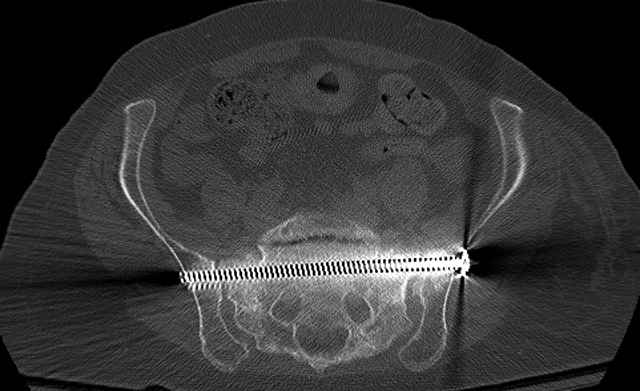

Here are a recent patient’s example slides...

Pelvic CT Scan - 3 Months After Fall

Sacral Injuries

Ramus Fractures

Percutaneous Fixation

(B) Ramus-Retrograde

2 TransIliac-TransSacral

Upper Segment